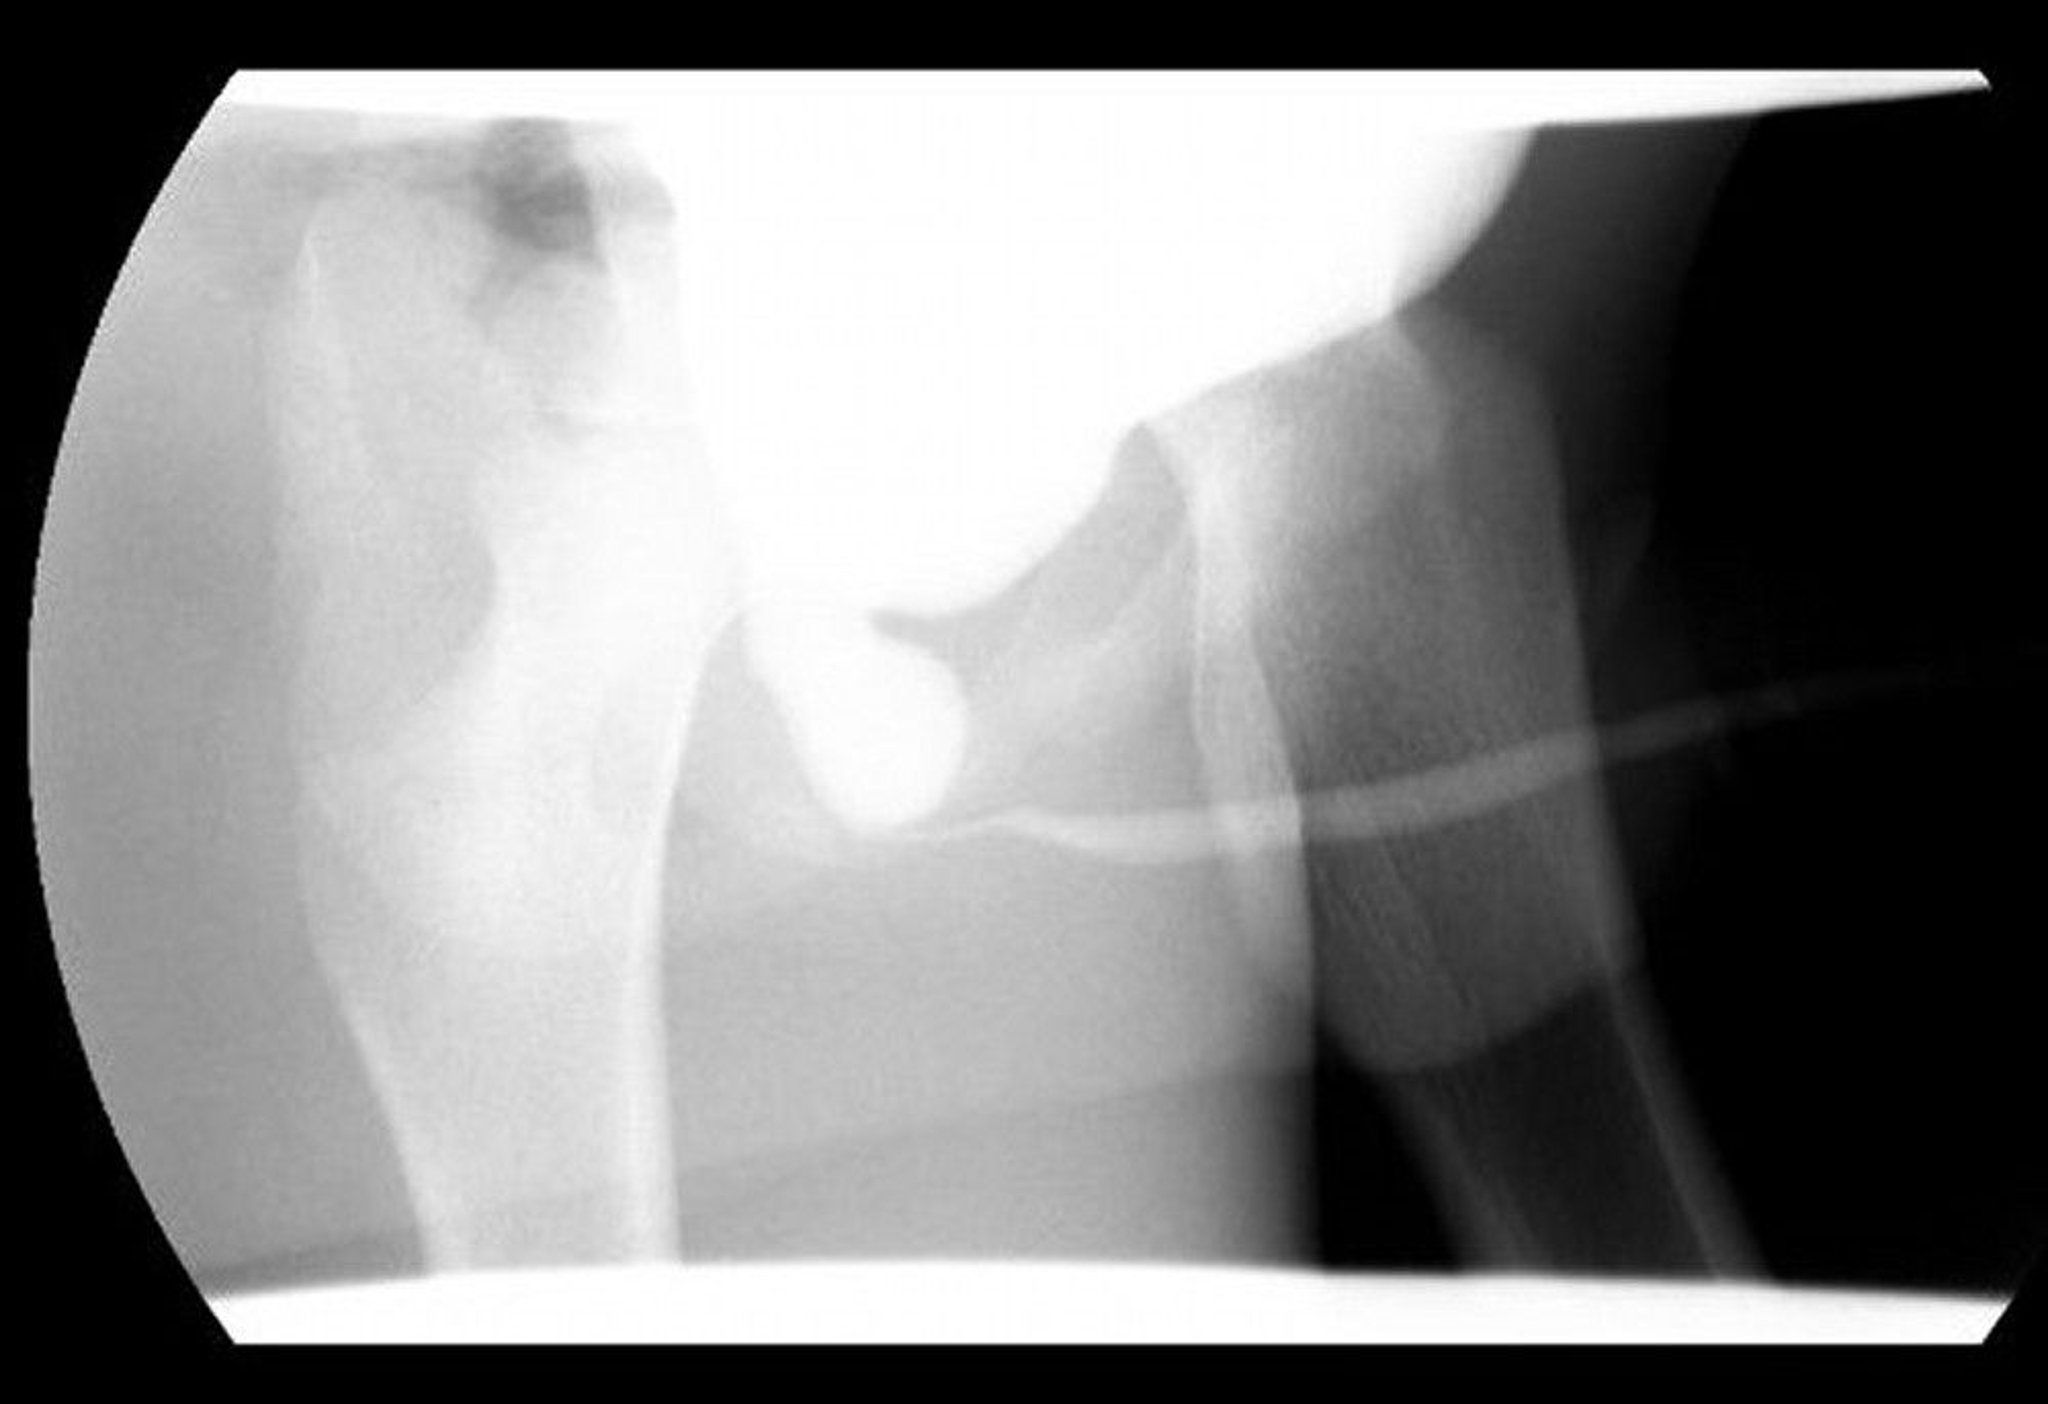

この排尿時膀胱尿道造影(VCUG)像には,後部尿道弁による遠位の閉塞を伴う後部尿道の拡張が写っている。

Image courtesy of Drs.Ronald Rabinowitz and Jimena Cubillos.